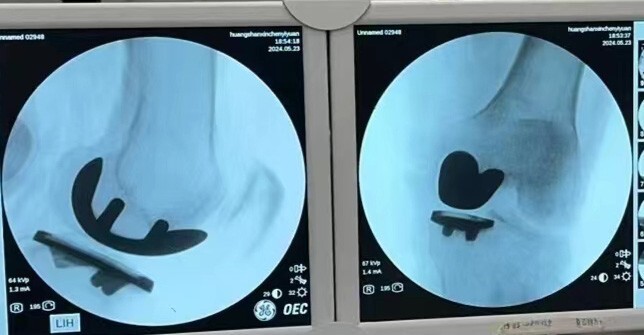

第3例:机器人辅助下左膝内侧单髁关节置换术

来自祁门的许某某在10年前就出现了左膝关节疼痛,期间多次就医,各种治疗也都尝试过,效果均不怎么理想。今年过完年,左膝关节疼痛加剧,已经严重影响生活质量,于是前来新晨医院就诊,检查后以“左膝骨性关节炎”住院治疗。

术中,经过机器人的准确定位,骨科手术团队的通力合作下,手术顺利,术后片子显示,假体植入位置准确,术后预期不错。